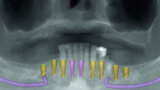

Fig 5 Analyse dento-faciale du traitement implantaire proposé dans l’arcade maxillaire